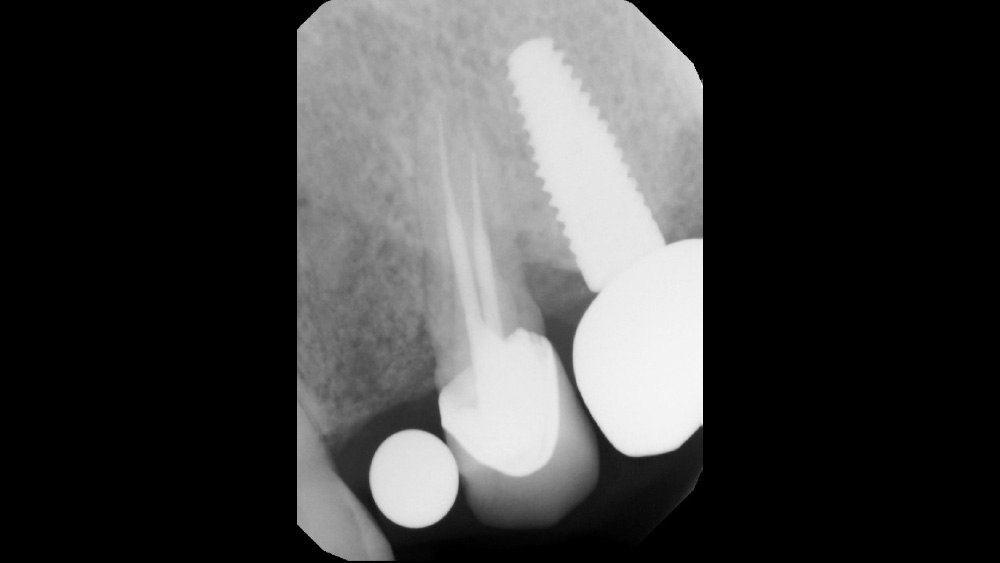

After gaining a clear understanding of the available hard and soft tissue through intraoral evaluation, radiography and — when possible — CBCT scanning, the clinician can determine whether flap reflection or a flapless surgical procedure is ideal for the individual patient. Both of these surgical techniques offer advantages, and the approach should be determined based on the amount of attached tissue present at the implant site, as well as the volume of bone.

The following case, which I performed alongside Dr. Stephanie Tilley of Pensacola, Florida, illustrates the use of both surgical techniques for the same patient, who presented with edentulous spaces in the areas of both right and left maxillary first bicuspids. Due to varying soft-tissue volume on each side of the arch, implant surgery was performed using a flapless procedure for one site, while the attached gingiva was reflected to expose the available hard tissue for the other. As a result of proper site evaluation, treatment planning and restorative-driven implant placement, both surgical techniques led to successful outcomes for the patient.